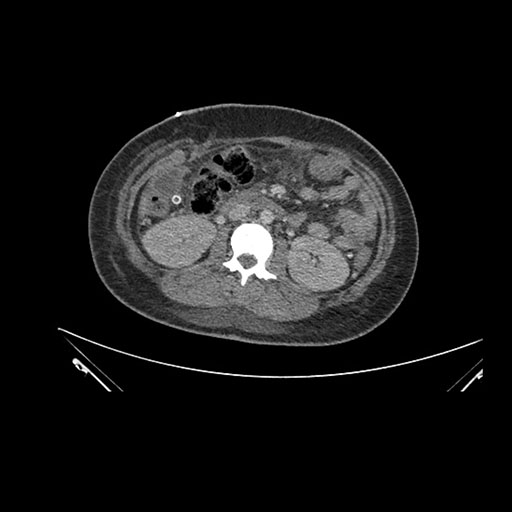

Axial Arterial

Axial Venous

Imaging analysis

Based on initial findings, which issue(s) would you be most concerned about?